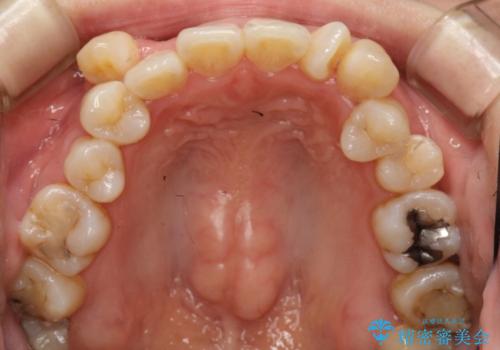

初診時の歯並びの状態としては、上下に強いガタガタがある状態であり、それが原因で口腔内の清掃状態も極めて悪い状況でした。

スペースの不足量が著しく、上下左右の抜歯を伴うワイヤー矯正にて治療を行いました。

また、左上の奥歯に関して親知らずの1つ手前の歯の状態が悪かったため、その歯は抜歯をし親知らずを利用して噛み合わせを作りました。